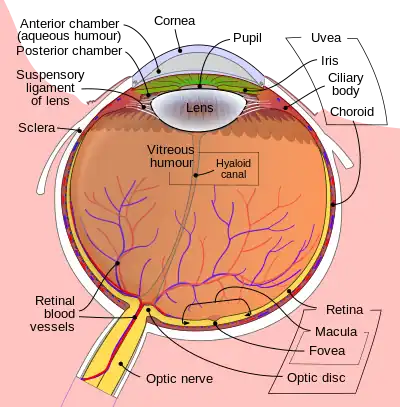

Schematic cross section of the human eye; choroid is shown in purple.

Schematic cross section of the human eye; choroid is shown in purple. Laser Doppler imaging of retinal and choroidal blood flow

The interior of the posterior half of the left eyeball Structures of the eye labeled

Structures of the eye labeled This image shows another labeled view of the structures of the eye

This image shows another labeled view of the structures of the eye Calf's eye dissected to expose the choroid: its tapetum lucidum is iridescent blue